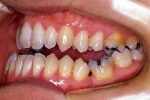

| マルチブラケット終了時

|